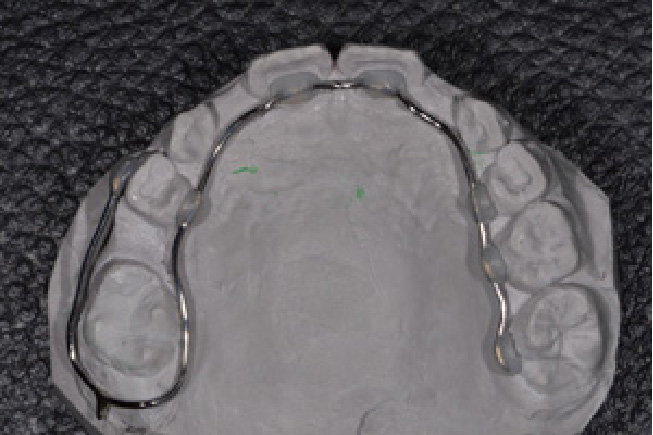

• 予防矯正

歯並びの改善や、筋機能改善(適応年齢3~17歳程度)

歯ならびだけでなく、口の周りや舌の筋肉の機能の改善。正常な成長発育を促す予防的な矯正治療。

【自費診療:プレオルソ:55,000円、交換:11,000円、 床矯正、その他装置 77,000円~】